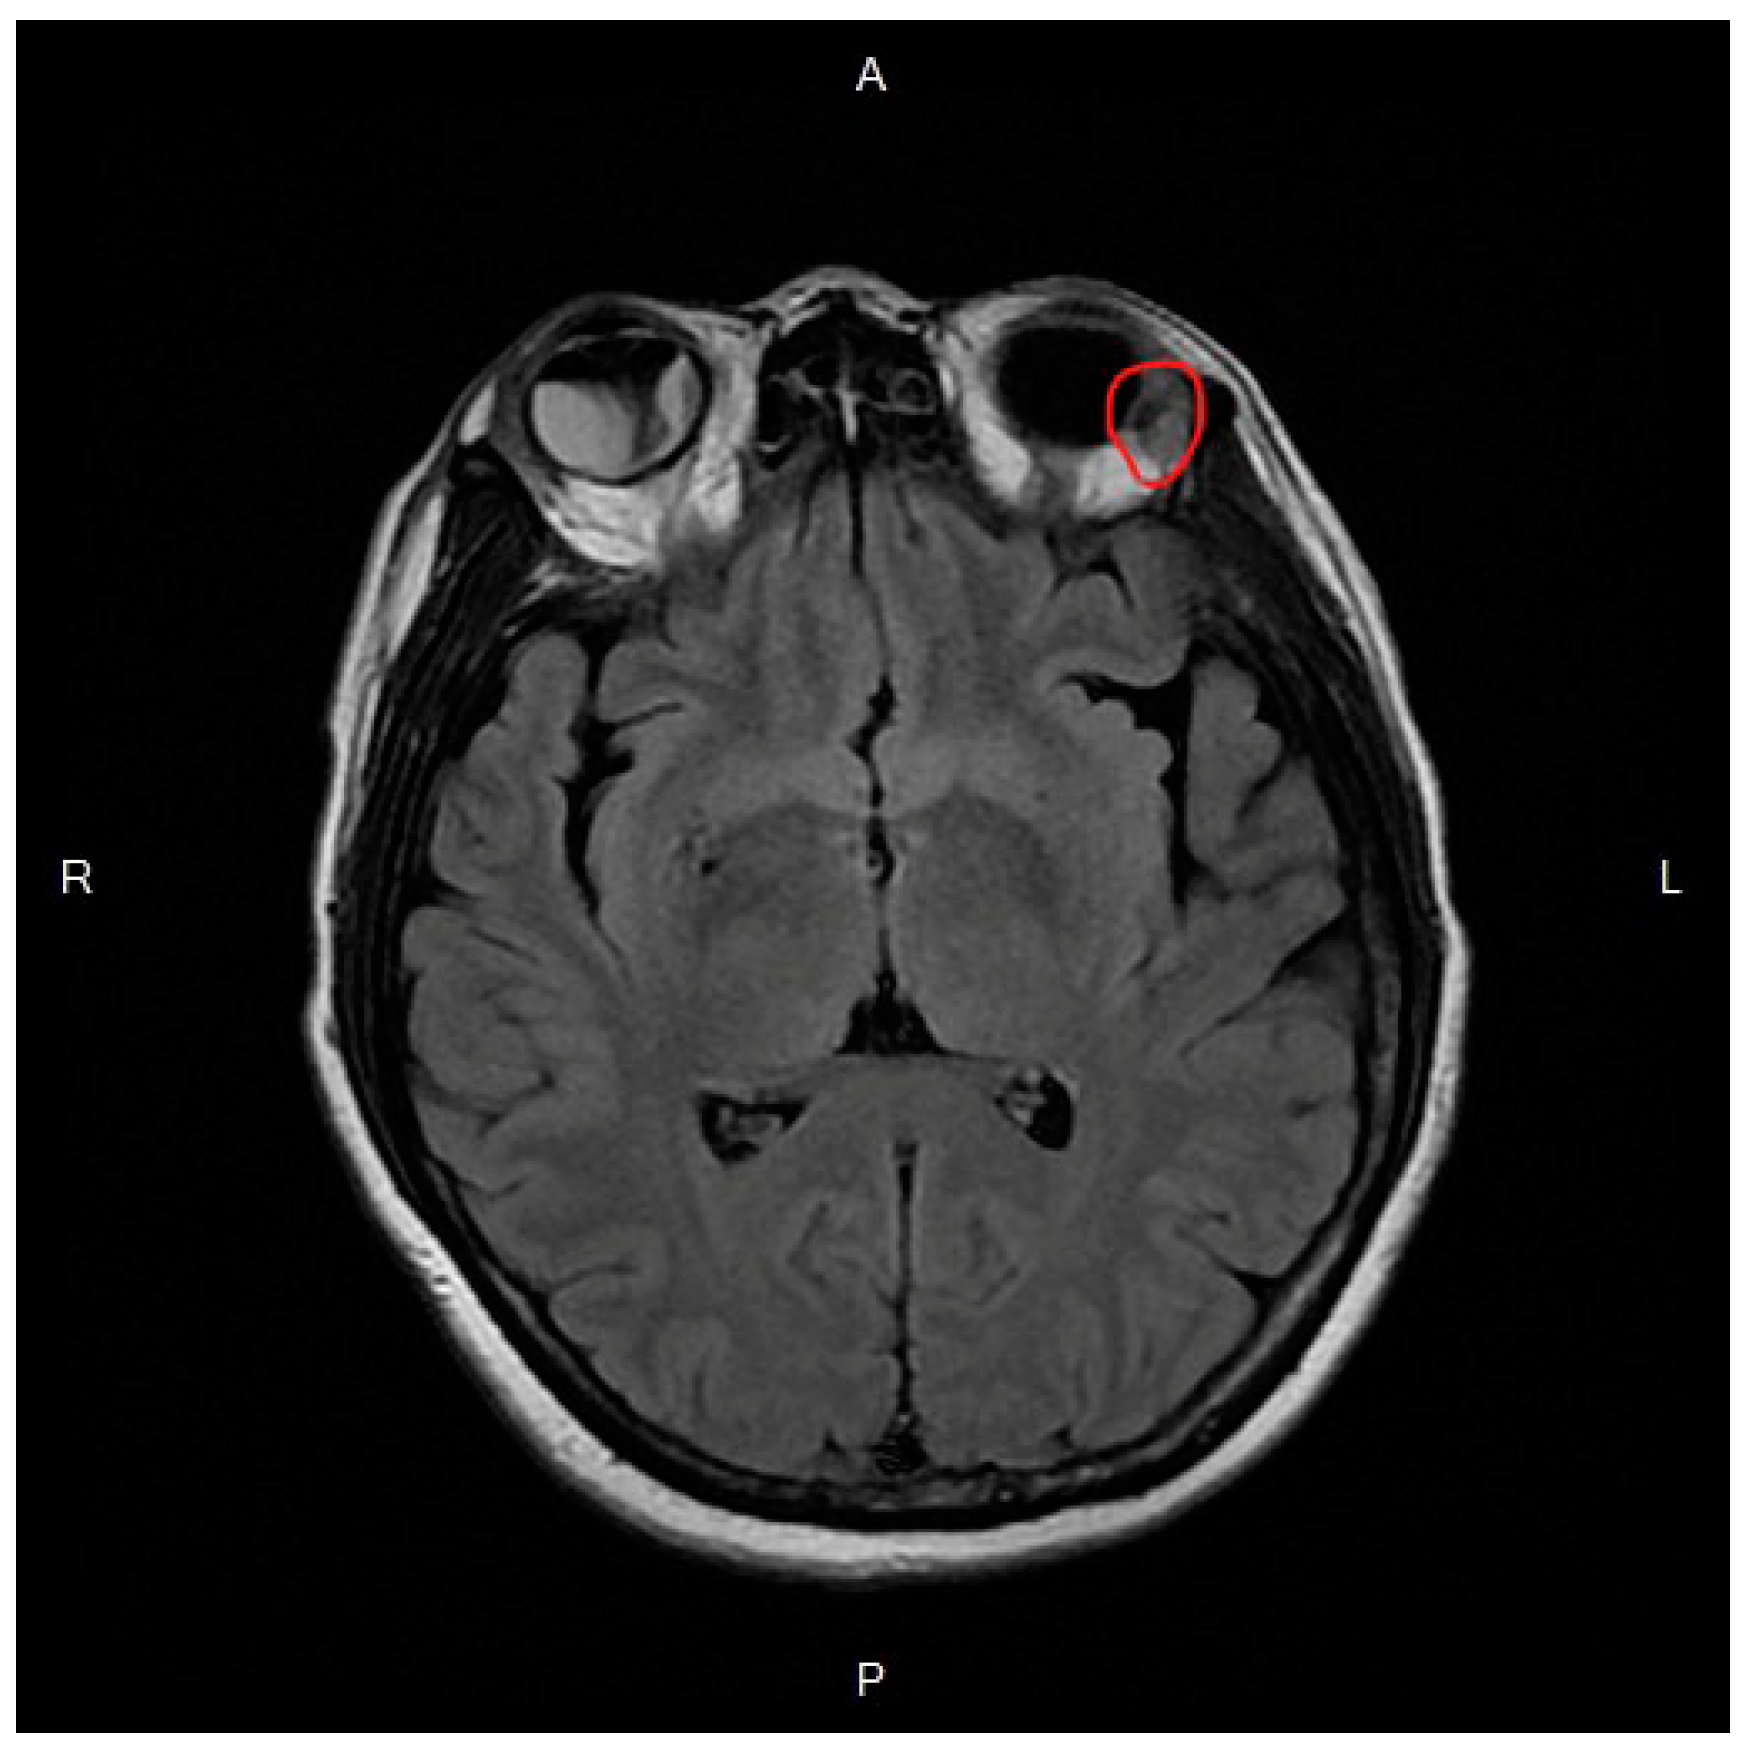

2. Case Report